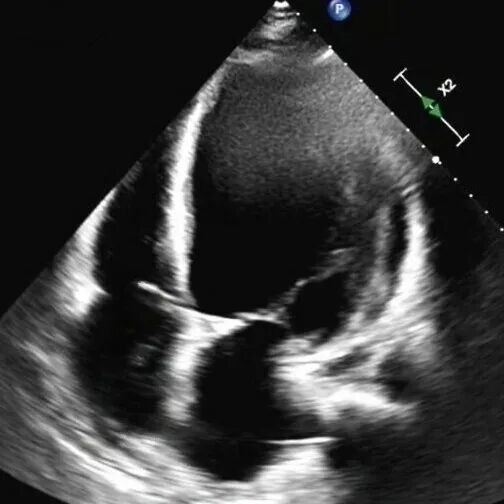

61岁的李先生(化名)三年前就偶尔出现胸闷乏力,一个月前,他因夜间无法平卧、呼吸极度困难,被紧急送往beat365在线唯一官网第一附属医院(第一临床医学院)心脏重症监护室。通过系统检查,李先生左室舒张末期内径102mm(男性的正常值≤55mm),主动脉根部瘤样扩张63mm(正常≤35mm),左室射血分数仅21.83%(正常≥50%),心功能IV级(NYHA分级),主动脉瓣重度关闭不全,二尖瓣轻-中度关闭不全,最终确诊为终末期心衰,巨大心脏,主动脉根部瘤样扩张,随时发生主动脉夹层/主动脉破裂危及生命,此外主动脉瓣重度关闭不严,心功能极差,心脏随时可能“停摆”。

术前心脏超声